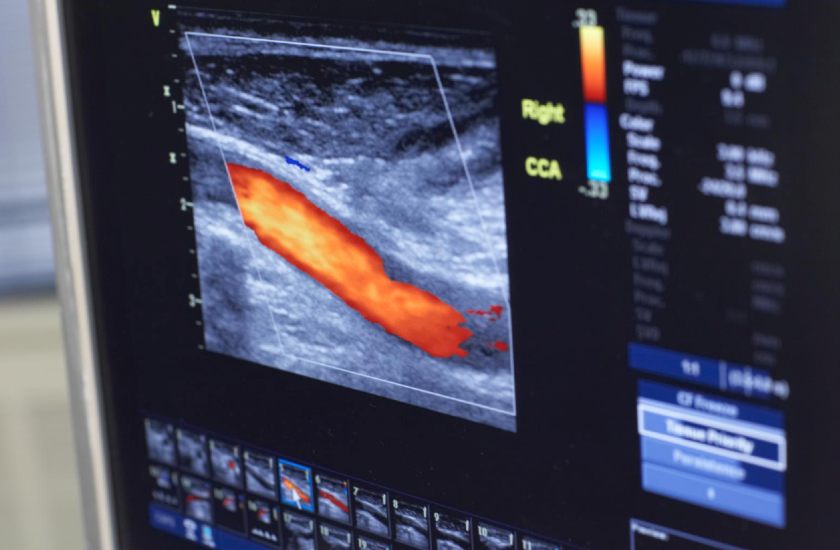

Some of the common forms of medical imaging are CT scans, MRIs, ultrasound and X-rays.

• Ultrasounds use high-frequency sound waves to monitor a developing baby’s health, diagnose heart conditions and guide biopsies, among other uses.

• Angiography — imaging of blood vessels and the heart